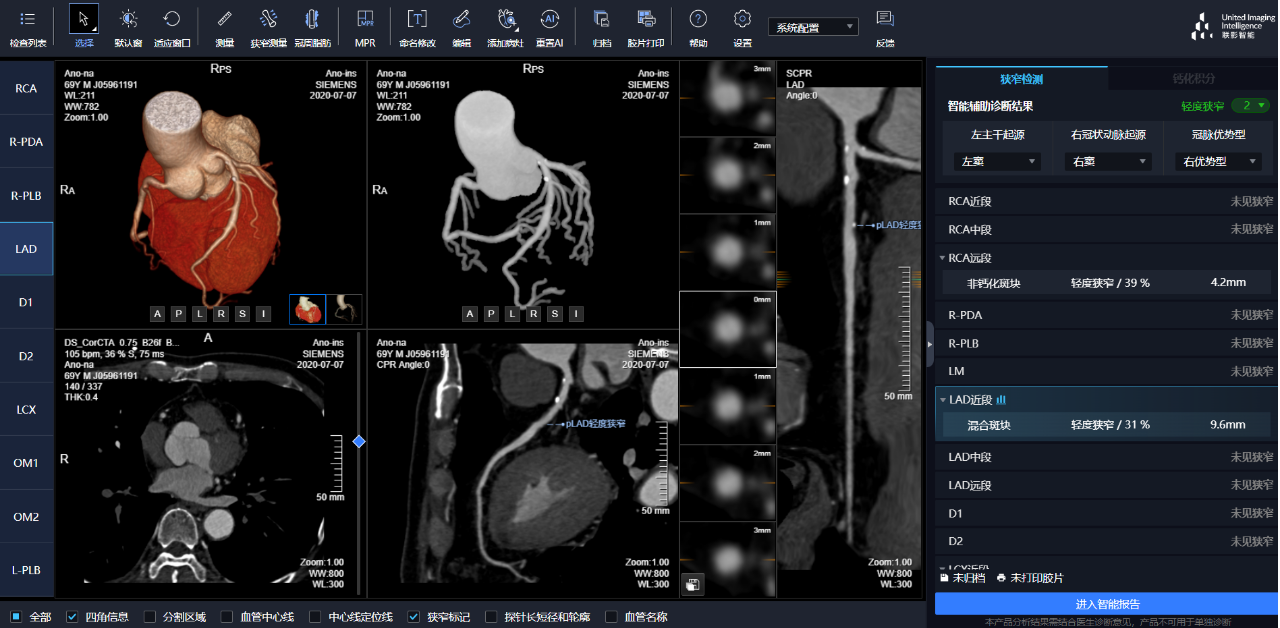

相較于傳統(tǒng)人工閱片,在聯(lián)影智能AI軟件的輔助下,640CT閱片的靈敏度和閱片效率均有顯著提升,對(duì)于細(xì)微骨折乃至于隱匿性骨折的判斷,準(zhǔn)確度更高,極大地減少了漏診及誤診。

通過(guò)3D視圖可任意旋轉(zhuǎn)觀看血管全貌,AI秒級(jí)實(shí)時(shí)計(jì)算重建血管,可實(shí)現(xiàn)多維輔診包含:板塊定性定量分析、狹窄評(píng)估、心肌橋檢出、支架檢出、鈣化積分,全程AI關(guān)注心血管健康。